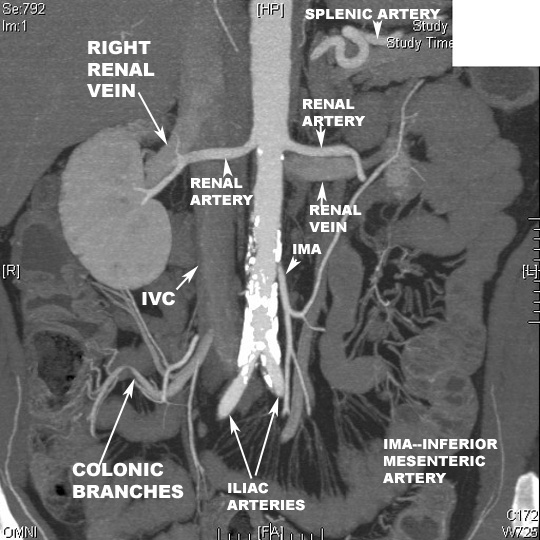

Renal arteries arise from the abdominal aorta at about L1 or L2, below the origin of the superior mesenteric artery.

They arise from the lateral surface of Aorta

Right renal artery passes behind the inferior vena cava to reach the right kidney

There can be more than one artery